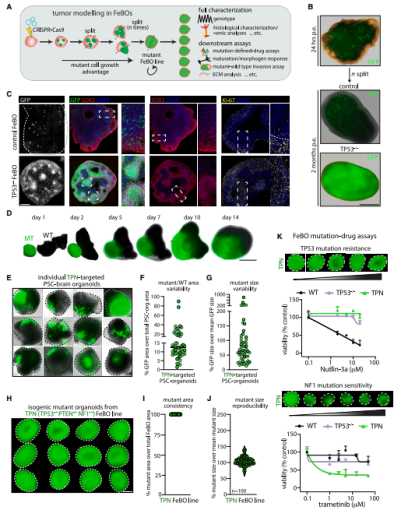

CRISPR 編輯的 FeBOs 細胞系可用於腦腫瘤建模

考慮到組織衍生類器官快速擴張的能力,該團隊進一步研究了它們在腦癌建模方面的潛力。研究人員使用基因編輯技術 CRISPR-Cas9 在類器官中的少數細胞中引入了眾所周知的癌症基因 TP53 的缺陷。三個月後,TP53 缺陷的細胞在類器官中完全超過了健康細胞,這一結果意味著它們獲得了生長優勢,這是癌細胞的典型特徵。

然後,他們使用 CRISPR-Cas9 來關閉與腦腫瘤、膠質母細胞瘤相關的三個基因:TP53、PTEN 和 NF1。此外,研究人員還利用這些突變的類器官來觀察它們對現有抗癌藥物的反應。總之,這些實驗顯示了類器官在癌症藥物篩選方面的潛力,還可以將某些藥物與特定的基因突變聯繫起來。因此,FeBOs 搭建了一個通用的腦腫瘤建模平臺。